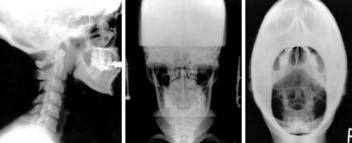

Atlas Orthogonal é um procedimento desenvolvido por Roy Sweat em 1980 que tem como base o procedimento de John F. Grostic, que criou um sistema de quantificação da subluxação do atlas. O procedimento de avaliação requer …